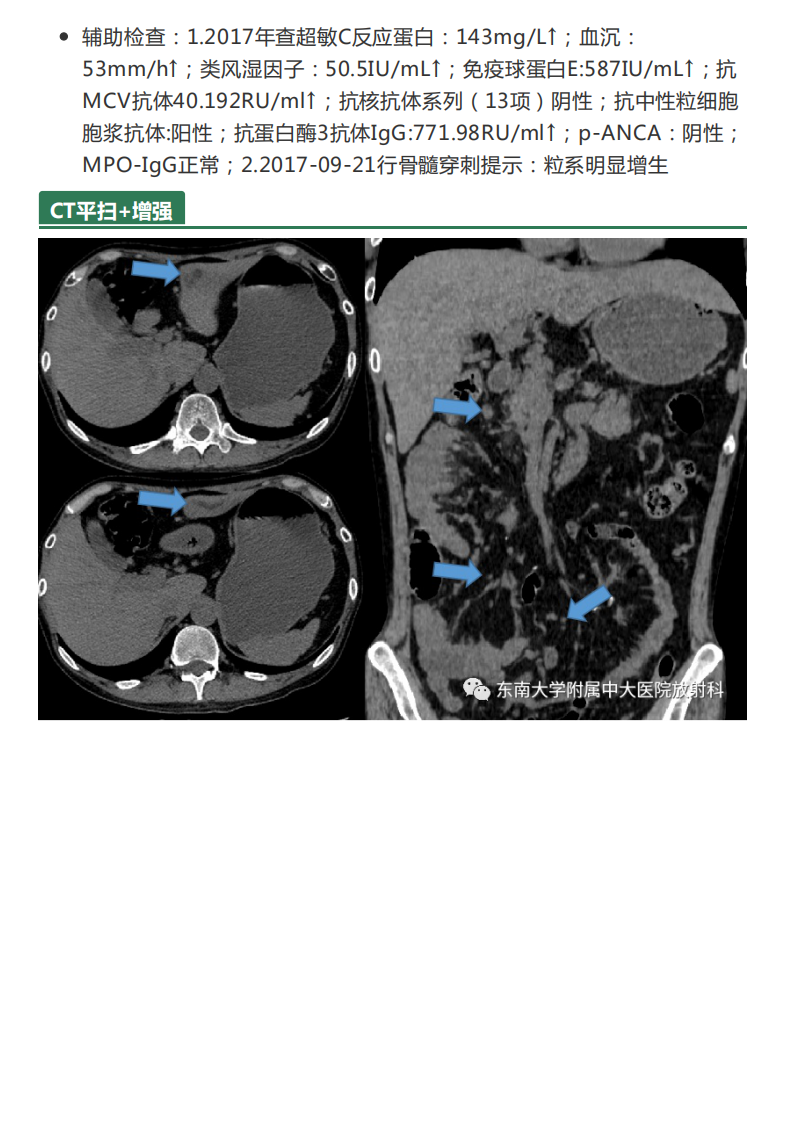

20210621_3【晨读结果公布】2021.06.21消化系统疾病——病例1HELLP;病例2:ANCA相关性血管炎;病例3:原发性肝癌.pdf